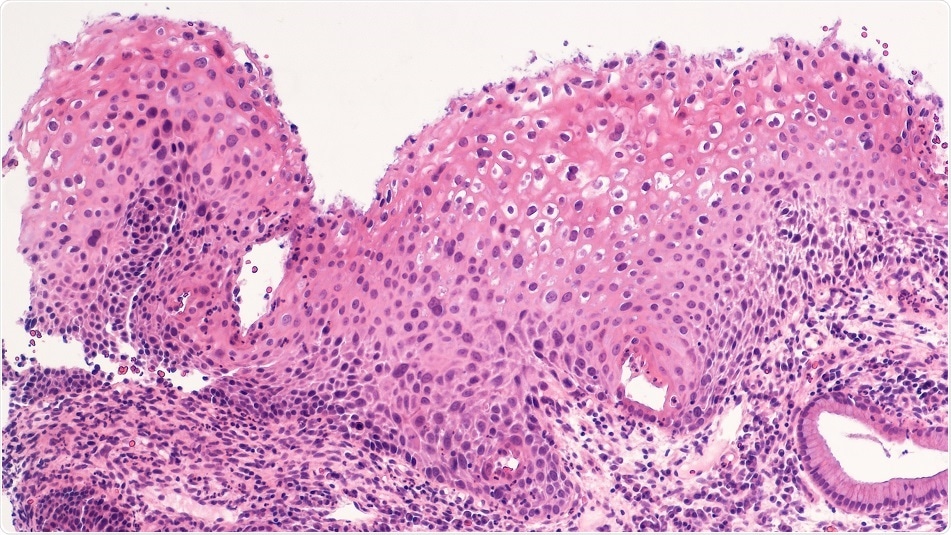

Credit: David Litman/ Shutterstock.com